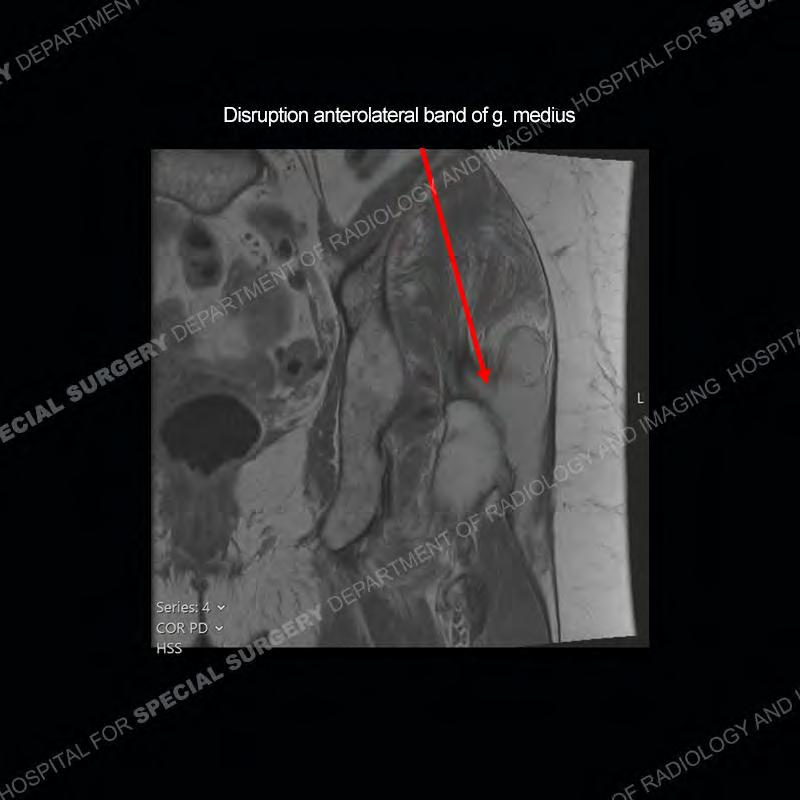

The radiograph is not particularly contributory in this case. The MRI demonstrates markedly abnormal architecture of the gluteus minimus and anterolateral band of the gluteus medius. Portions of the tendons are high signal, portions are highly attenuated, and portions are disrupted. A large, complex fluid collection is present in the adjacent soft tissue.

Diagnosis: Gluteal Tendinosis and Disruption with Complex Trochanteric Bursal Collection

Not as much of a diagnostic dilemma as many of the other cases shown but just a nice example of the pathology seen of the gluteal tendons and a cause of trochanteric pain. Although, frequently thought of in isolation, trochanteric bursitis or bursal thickening is much more commonly a reactive change to underlying pathology of the subjacent gluteal tendons. The gluteus medius is divided into a posterior band and an anterolateral band. Tendinosis and partial tearing very commonly will involve the gluteus minimus and especially the more posterior fibers and then propagate into the anterior lateral band of the gluteus medius. Involvement of the posterior band of the medius is much less common and engenders a marked degree of functional impairment.